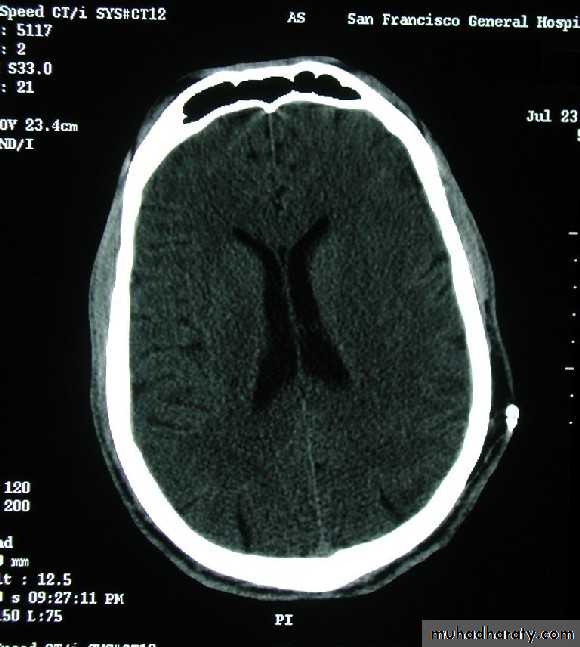

Acute subdural hematoma

Subacute subdural hematomaChronic subdural hematoma